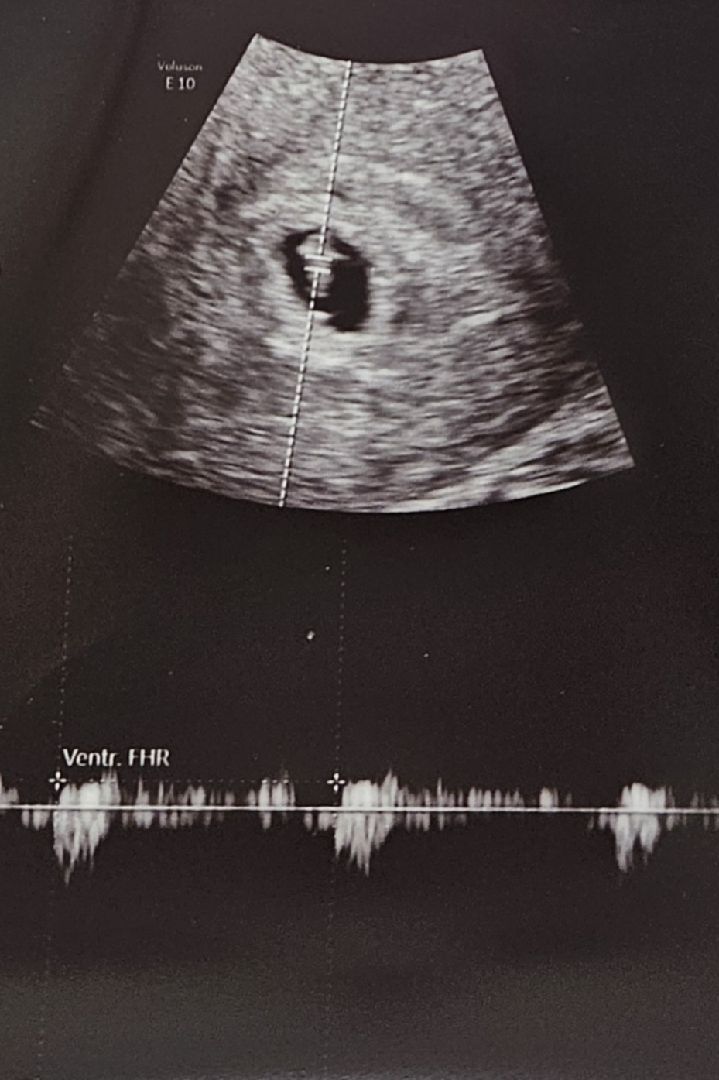

초음파 볼 때마다 예정일이 달라져요~ 오늘 6주 4일차여서 심장소리 들으러 갔어요. 3일 전부터 피비침이 조금씩 있었고 배도 싸르르 했어요. 양은 점점 많아지고 처음에 선홍색, 갈색 피였으나 점점 붉은 피로 바뀌었습니다. 생리대를 하고 있어도 불안하지는 않았어요. 아이가 잘 버텨줄거라 믿었습니다. 저는 종합병원으로 다녀서 초음파를 다른곳에서 보고 진료를 들어가는데 초음파선생님이 인상을 쓰시며 여기저기 초음파를 하시더며 제가 출혈이 있다고 해도 아무대답을 안하시다가 갑자기 보호자 들어오라는거예요. 가슴이 철렁했습니다. 그런데 남편이 오자 심장소리를 들려주는거예요. ( 산모들은 이 시기가 예민한데 부드럽게 말씀을 해 주시는 분은 아니신거예요ㅜㅜ) 87bpm이라고 하면서 조금 느리다고 했어요. 순간 안도가 되면서 눈물이 나오고 말았어요. 진료를 들어갔는데 선생님께서 1차 고비(심장소리)는 지났다고 하시고요. 피 비침은 이 시기에 많다고 하시네요. 움직이면 더 많이 생긴다고 눕눕하고 있으래요. 초음파에 6주 1일로 오늘부터 심장이 뛰는거라 87bpm이라고 하시며 점점 빨라질거라고 하셨어요. (아기들은 110정도 된다네요 ) 지금 시기는 엄마가 잘 못해서 유산하는 시기가 아니라고 하시면서 아이랑 엄마랑 계속 소통하면서 아이가 건강하지 않으면 엄마 몸에서 아이를 받지 않으려고 한다고 이야기해주셨어요. 엄마가 일해서, 못 쉬어서, 관리를 못해서가 아니래요. 전 여전히 붉은 피가 비추고 있지만 아이를 믿고 눕눕해보려고 합니다. 2주(8주까지) 뒤에 잘 자라고 있으면 유산이 잘 되는 시기는 지나는 거래요~ 여러분 우리 걱정보다는 믿음으로 이 시기를 잘 보내 보아요^^